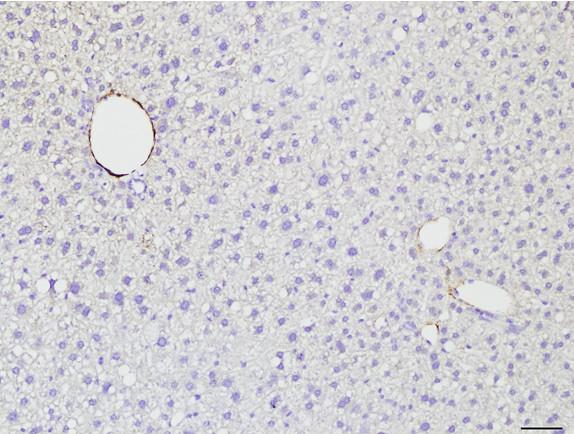

Figure 6: Histopathology for C57BL/6NTac mice placed on D09100310 diet (MASH B6NTac) or kept on chow diet (Control B6NTac) from 6 weeks of age. Animals were on diet for 27, 35 or 53 weeks. Hematoxylin and eosin (H&E) staining illustrates morphological changes including steatosis and infiltration of immune cells. Activated HSCs were identified in liver sections by using a rabbit polyclonal antibody to alpha-smooth muscle actin (a-SMA) (1:500 dilution; ab5694; Abcam, Cambridge, MA) which was detected by an anti-rabbit IgG embedded polymer with embedded horseradish peroxidase and visualized with 3,3′-diaminobenzidine (DAB) chromogen (Agilent, Carpentaria, CA). Hepatocellular lipid droplets were identified by visualization of the lipid-binding protein adipophilin known to be expressed in steatotic livers. Sections of livers were probed using a rabbit polyclonal anti-adipophilin antibody (1:200 dilution; NB110-40877, Novus Biologics, Littleton, CO) which was detected by an anti-rabbit IgG embedded polymer with embedded horseradish peroxidase and visualized with 3,3′-diaminobenzidine (DAB) chromogen (Aligent, Carpentaria, CA). Picrosirius red (PSR) staining illustrates collagen I and III fibers and is used to measure fibrosis. The same individual MASH or control animal is shown for all four stains in a particular time point. Different individual animals were used for each time point (i.e. data is not longitudinal by animal). Histopathology services provided by IDEXX BioAnalytics.